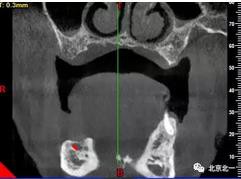

術(shù)前檢查片下頜骨季度萎縮,右側(cè)下頜下牙槽神經(jīng)管幾乎位于牙槽嵴頂。不能行常規(guī)種植。采用A04技術(shù)可實(shí)現(xiàn)即即刻種植一日戴牙夢(mèng)想。

圖一至圖六明顯看出右側(cè)頦孔位于牙槽嵴頂。很清晰看出頦孔區(qū)的U型形狀。